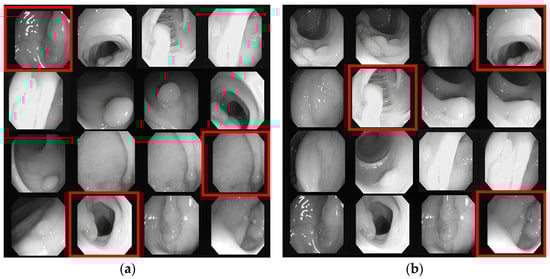

5.4.2. CVC-ClinicDB Dataset

- Top DSC samples: The ground mask sections of the polyp area are shown in blue boxes in Figure 13a, which shows the prediction of the selected top three samples. In oversaturated data (first row), most models failed to correctly identify the precise polyp area because of high contrast on the image. The IRv2-Net and TTA models correctly identified the mask, whereas others failed.

- Lowest DSC samples: The selected samples of lower DSC scores are shown in Figure 13b. The polyp masks created by the IRv2-Net + TTA model were superior to those created by other models. Remarkably, saturated (second row) and flat (third row) type polyps were accurately detected in the proposed model. Utilizing TTA, these predicted regions are more precisely reshaped by deleting excessive areas.

- Cross testing: The Kvasir-SEG dataset was tested to observe the model’s qualitative behavior. Then, Kvasir-SEG test samples were used to put these trained models to generate predicted masks. The expected outcomes based on unobserved data are shown in Figure 13c. For predicting unseen data, the IRv2-Net + TTA model showed better performance. Overall, our suggested approach considerably enhanced the quality of results for both datasets and cross-prediction.